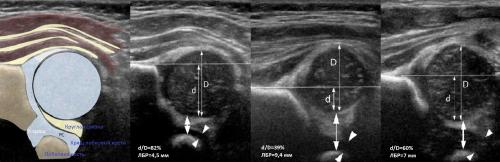

Датчик располагают в проекции большого вертела параллельно поясничному отделу позвоночника. Найдите самое глубокое место вертлужной впадины. Отрегулируйте наклон датчика, чтобы линия тела подвздошной кости лежала строго горизонтально (2).

Проведите базовую линию по наружному контуру подвздошной кости и обозначьте головку бедренной кости, аппарат автоматически вычисляет степень костного покрытия головки. Костное покрытие головки в случаях предвывиха 40-50%, подвывиха

Линии костной (красная) и хрящевой (зеленая) крыши проходят через костный выступ, а так же начало Y-хряща и центр гиперэхогенного кончика суставной губы, соответственно. Степень развития костной крыши определяет ∠α, а хрящевой крыши ∠β.

Если край подвздошной кости округлый, костный выступ определяют в точке перехода дуги наружного контура вертлужной впадины в дугу наружного контура подвздошной кости. Обратите внимание, все линии проходят по наружному контуру костей.

Тип 1 : ∠α>60°, костное покрытие головки >50%

Тип 2 : 43°

2a : 50°

2b : 50°

2c : 43°

2d : 43°77°. Костная часть крыши уплощена. Костный выступ закруглен или плоский. Хрящевая крыша расширена. Заключение: Тяжелая дисплазия т/б сустава (тип 2d), предвывих (близко к децентрации головки). Гипсовая повязка на 3 недели, затем стремена Павлика. Контроль УЗИ 1 раз в месяц.